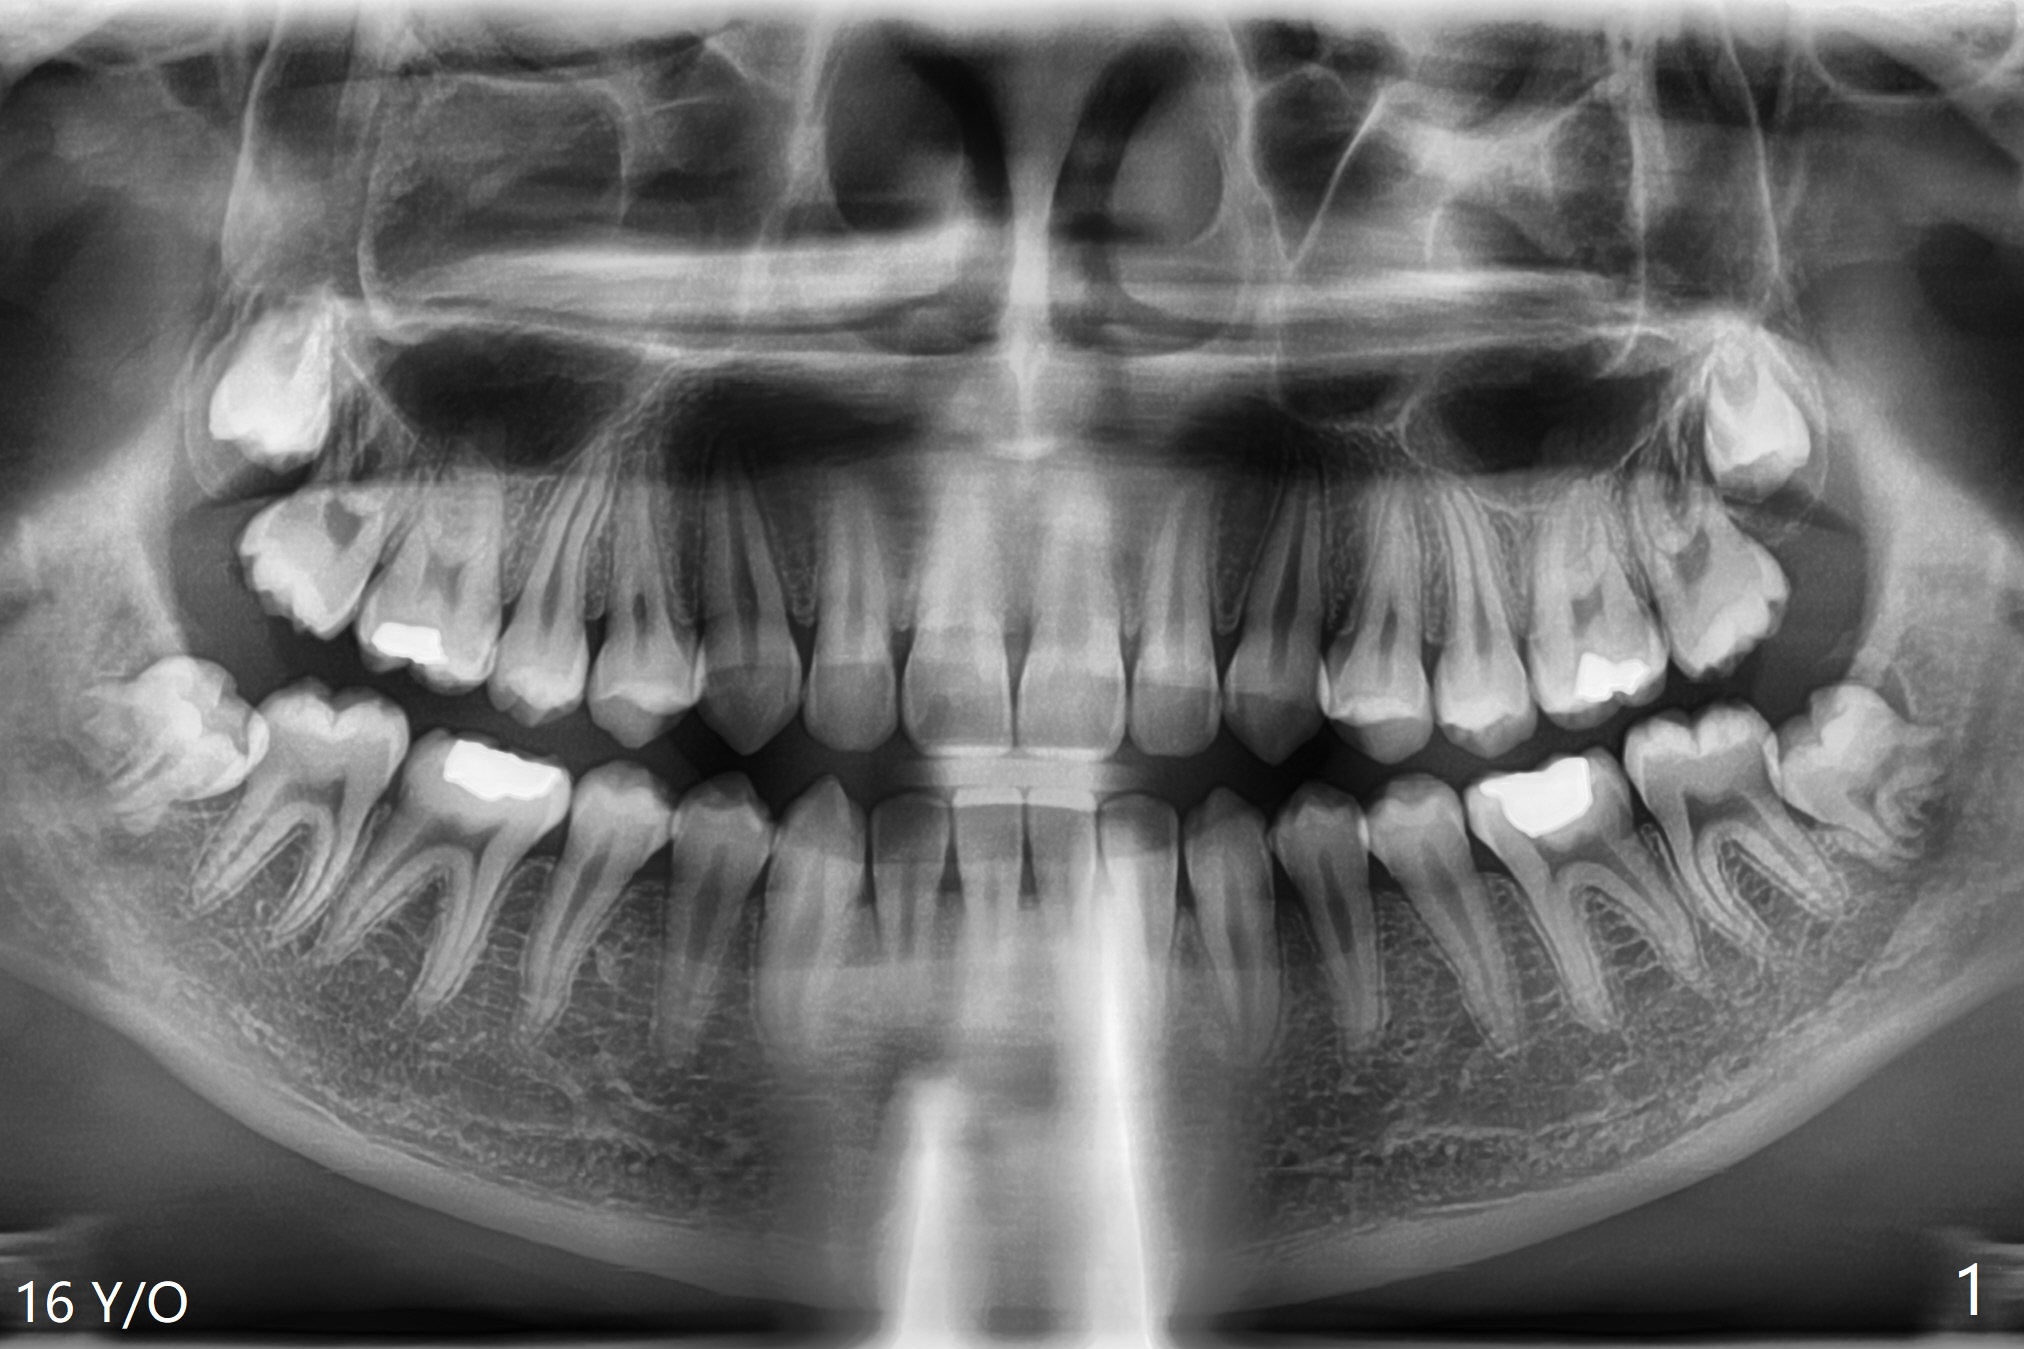

左下智齿疼痛(图一),截骨后牙齿容易松动,然后切断两次,顺利拔除,放置Osteogen Plug,4-0 铬羊肠线缝合(图二)。5个月后另外三个智齿拔除(右下放置胶原塞;上智齿拔除盲目,困难,稍微早些),左下智齿牙槽窝愈合(图三);近中牙槽嵴重建。